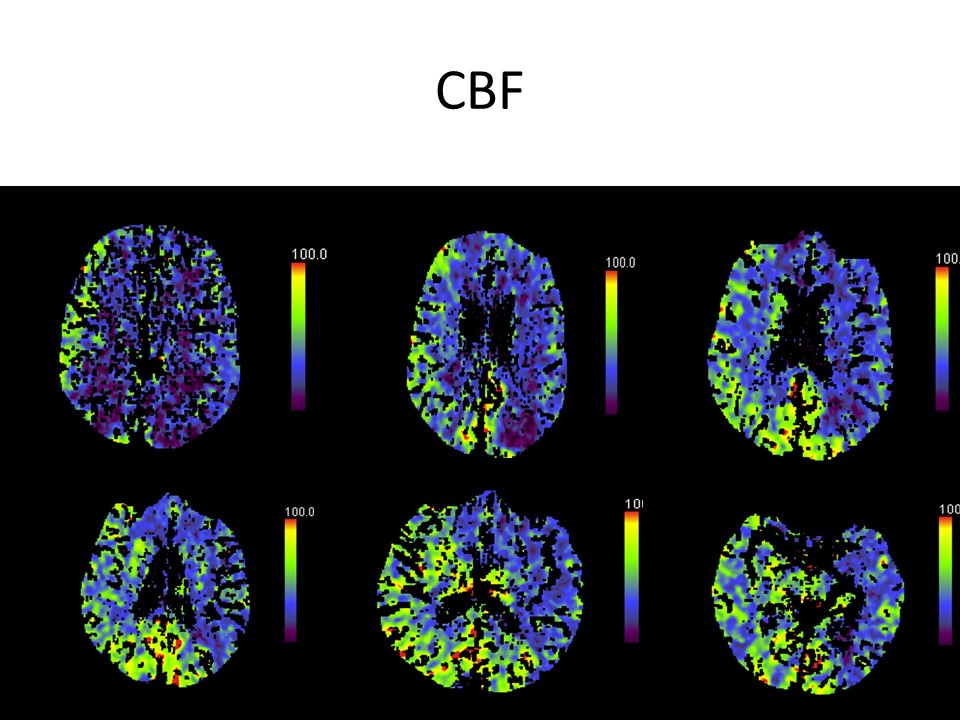

El estudio de la perfusión cerebral pone de manifiesto.

Un extenso territorio de retraso en mapas de tiempo a nivel de la totalidad del territorio de ambas carótidas con relativa área respetada a nivel de la circulación posterior.

Los mapas de volumen presentan algunas zonas parcheadas de menor perfusión.